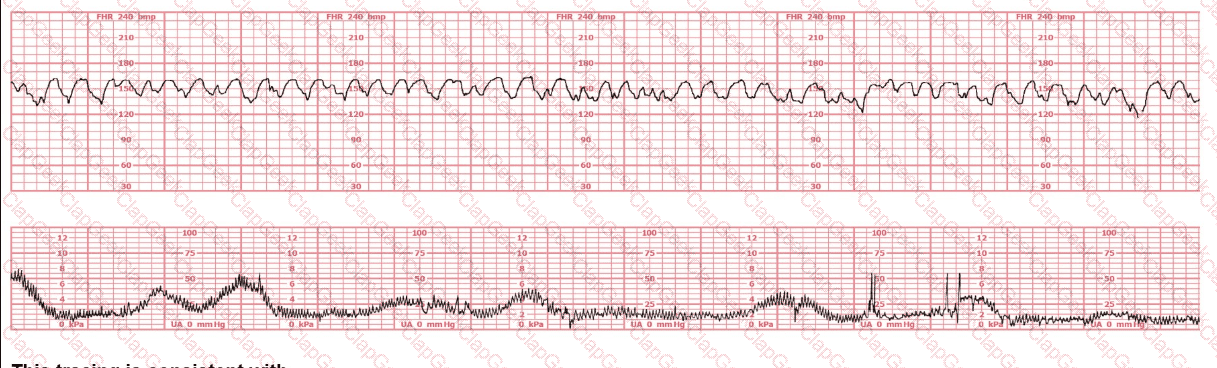

The decelerations seen in the fetal monitoring tracing shown are best described as: